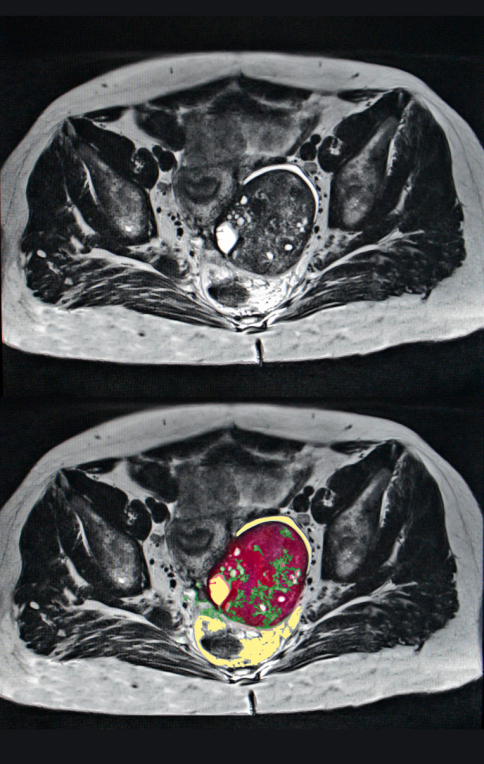

(৭) ওভারিয়ান সিস্ট নির্ণয়

ওভারিয়ান সিস্ট নির্ণয়ের জন্য চিকিৎসকরা সাধারণত নিম্নলিখিত পদ্ধতি ব্যবহার করেন-

- আল্ট্রাসাউন্ড:

- এটি সিস্টের আকার, অবস্থান এবং প্রকৃতি (তরল-ভরা বা সলিড) নির্ণয়ের সবচেয়ে সাধারণ পদ্ধতি।

- CT স্ক্যান বা MRI:

- জটিল সিস্টের ক্ষেত্রে বিস্তারিত চিত্র পেতে এই পরীক্ষাগুলো করা হয়।